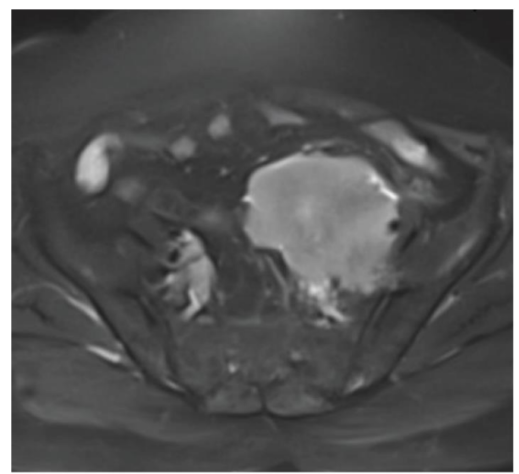

影像学检查提示双侧肾积水。CT 示输尿管周围见大小约9.2×7.8×7.8 cm不均质软组织肿块,包绕输尿管并伴中段输尿管节段性增厚;腹盆腔 MRI 显示左侧盆腔腹膜后见10.8×7.7×5.8 cm梭形分叶状肿块,包绕左侧髂内、外血管,浸润双侧远端输尿管并导致近端输尿管扩张,影像学提示恶性病变,首要鉴别诊断为尿路上皮癌与淋巴瘤。

图2:轴位T2压脂 MRI,示盆腔高信号肿块